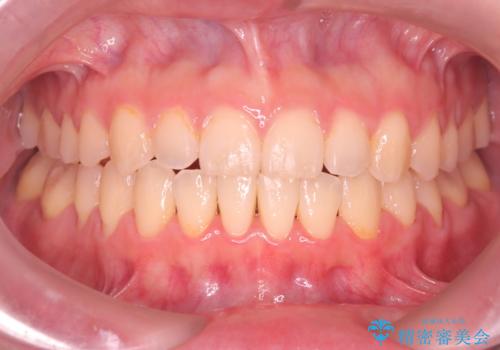

【ワイヤー矯正】がたつきを治したい